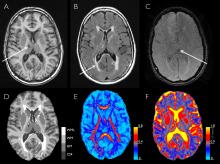

Regions of the brain function differently among people with post-traumatic stress disorder, causing them to generalize non-threatening events as if they were the original trauma, according to new research from Duke Medicine and the Durham VA Medical Center.